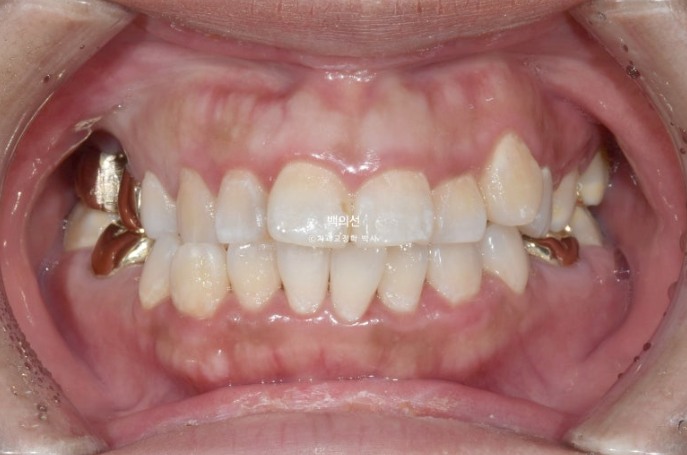

22년 12월 교정치료를 위해 내원한 환자분입니다.

고치고 싶은 것은 덧니 등 배열과 돌출입니다.

턱의 비대칭도 있어 앞니 치아중심선이 약 2mm 어긋나 있으며 아래턱이 돌아간 우측으로 송곳니와 어금니가 반대 교합입니다.

공간이 좁아 덧니도 있고

앞니 배열도 개선이 필요합니다.

웃을 때 잇몸이 많이 보이는 거미스마일도 심한 편이고

돌출이 심해 입술이 편하게 안다물어지는입술부전증도 보입니다.

입술부전증이 있으면 턱끝에 힘이 저절로 들어가게 되어 턱끝이 울퉁불퉁하게 보이는 호두턱 (호두주름)도 함께

나타나게 됩니다.

덧니도 있고 돌출도 심하니 작은어금니 4개 발치교정이 필요한 상황입니다.